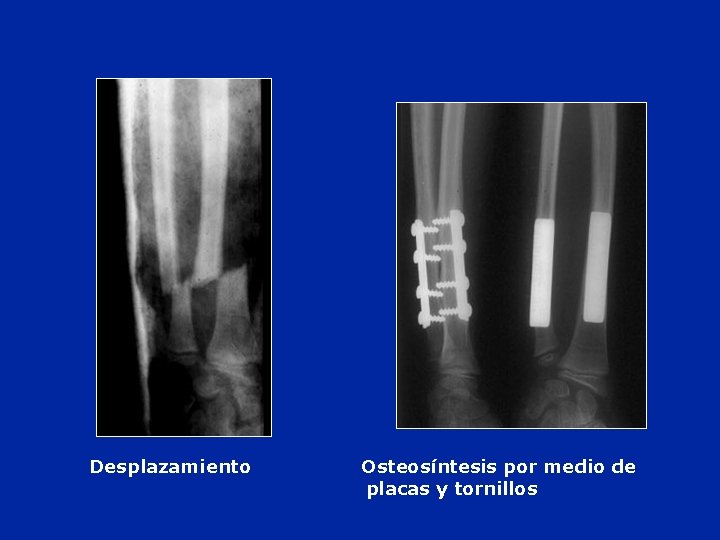

Desplazamiento Osteosíntesis por medio de placas y tornillos

Osteosíntesis de los 2 huesos del tercio distal del antebrazo Interposición muscular